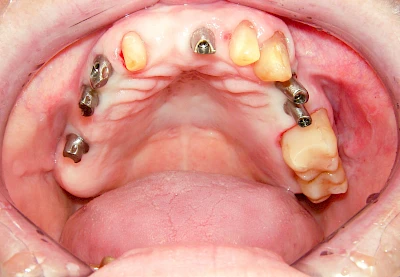

Fehlen einzelne Zähne und die Nachbarzähne sind unbeschadet oder gut zahnärztlich versorgt, werden immer häufiger Implantate gewählt, um die Lücken zu schließen. Auch bei größeren oder verteilten Lücken, wenn keine herausnehmbare Prothese gewünscht ist, werden Implantate für Kronen- bzw. Brückenversorgungen gesetzt. In Einzelfällen entscheiden sich sogar zahnlose Patienten für eine festsitzende Versorgung auf Implantaten.

Varianten zur Verankerung von festsitzendem Zahnersatz auf Implantaten